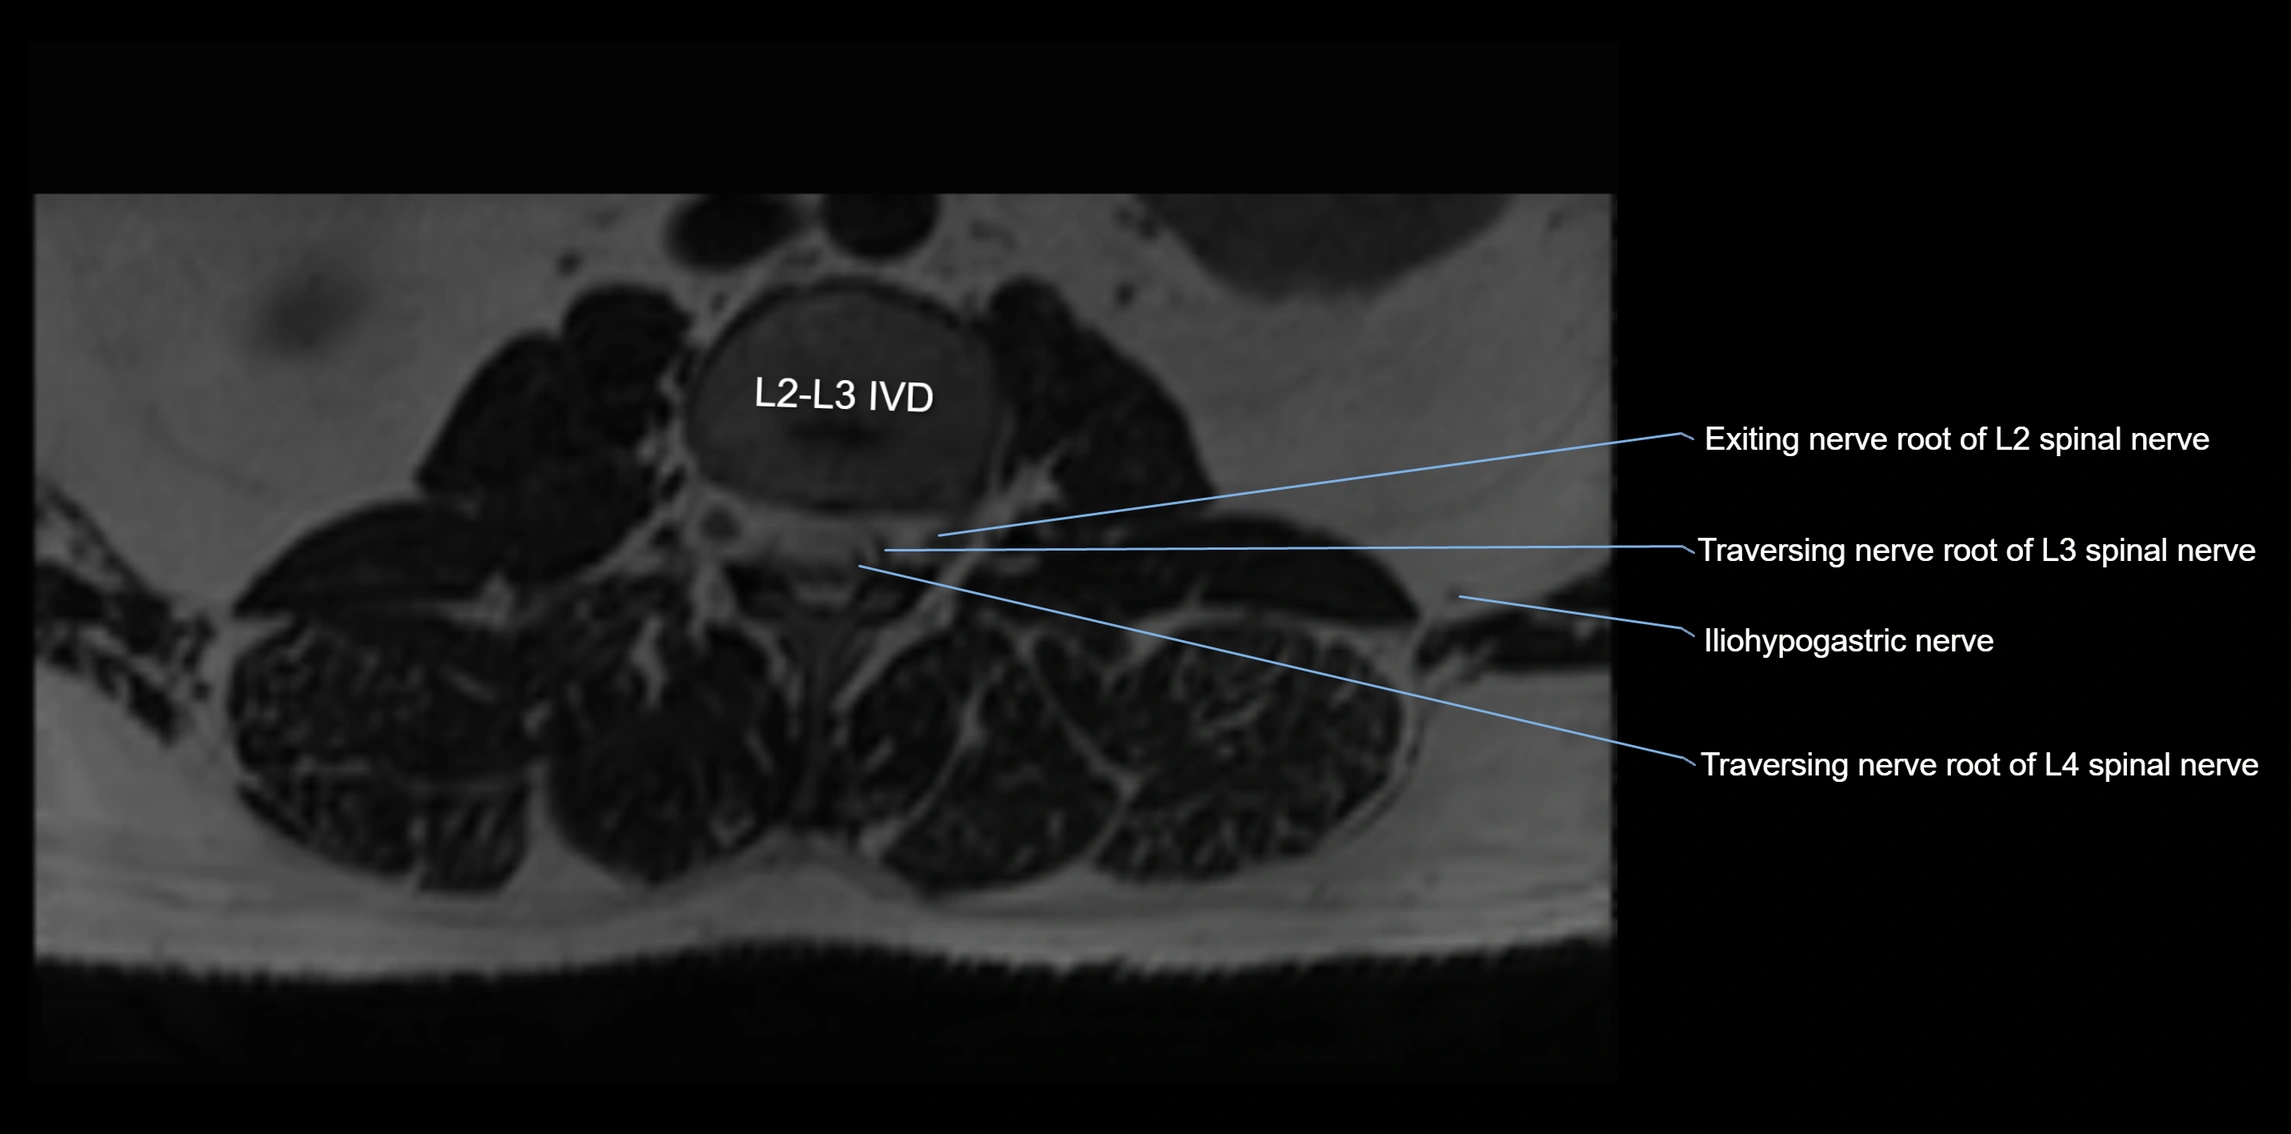

MRI Appearance

T1-weighted images:

• Nerve appears as a very thin low-to-intermediate signal intensity structure

• Surrounded by bright fat, aiding visualization

T2-weighted images:

• Nerve shows intermediate to mildly hyperintense signal compared to muscle

• Pathological involvement appears brighter

3D T2 SPACE / CISS:

• Nerve appears intermediate to mildly hyperintense compared to muscle

• Surrounded by bright fat or CSF, improving visualization

• Best sequence for mapping small pelvic nerves such as the anococcygeal

MRI image

image